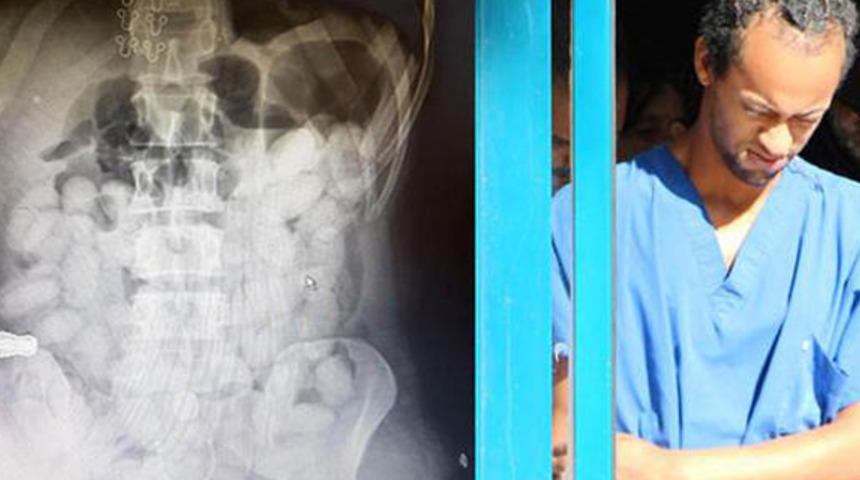

Antalya'da midesinde 59 kapsül içinde 649 gram kokain sokmaya çalışırken, yakalanan Brezilyalı Washington Lincoln Arves Tolentino (23), 25 yıl hapis ile 50 bin TL’lik para cezasına çarptırıldı.

Antalya İl Emniyet Müdürlüğü Narkotik Suçlarla Mücadele Şube Müdürlüğü ekipleri, 18 Ekim 2017 tarihinde,Brezilya’nın Sao Paulo kentinden İsviçre’nin Zürih şehri aktarmalı Antalya seferini yapan uçakla Türkiye’ye gelen Washington Lincoln Arves Tolentino’nun uyuşturucu kuryeliği yaptığı istihbaratı üzerine operasyon düzenledi. Antalya Havalimanı’nda önlem alan ekipler, uçaktan inen şüpheliyi gözaltına aldı. Mahkemeden alınan kararla hastanede yapılan iç muayenesinde, Tolentino’nun mide ve bağırsak kısmında, kokain içerdiği değerlendirilen kapsül şeklinde, çok sayıda cisim olduğu tespit edildi. Hastanede gözetim altında tutulan Tolentino’nun midesinde, 59 kapsül içinde, 649 gram kokain doğal yollarla çıkarıldı. Hastanedeki tedavisinden sonra emniyete götürülen Brezilyalı Tolentino, çıkarıldığı mahkemece tutuklandı.